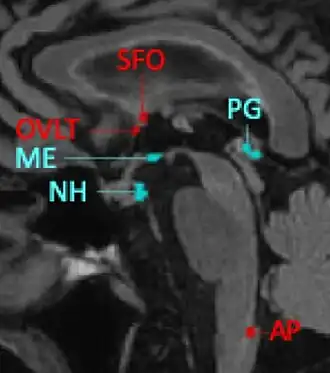

En 2021 se listaban como órganos neurohemáticos circunventriculares (NHO/CVO) a los siguientes: órgano vascular de la lámina terminal (OVLT), órgano subfornical (SFO), neurohipófisis (NHip), eminencia media (ME), órgano subcomisural (SCO), glándula pineal (PG), área postrema (AP). A estos se suma el Plexo coroideo (CP) que presenta caracteres similares.[9]

Los órganos neurohemáticos circunventriculares sensoriales (HMO-sn/CVO-sn) incluyen el órgano subfornical (SFO), el órgano vascular de la lámina terminal (OVLT) y el área postrema (AP).